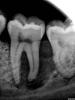

Каплан Опубликовано 19 июля, 2012 Поделиться Опубликовано 19 июля, 2012 Вообще там похоже есть линия перелома дистального корня. От фуркации и к дистальной пришеечной области. Ссылка на комментарий

Каплан Опубликовано 19 июля, 2012 Поделиться Опубликовано 19 июля, 2012 А линию отделяющую дистаьный корень только мне видно? Ссылка на комментарий

kriokov Опубликовано 19 июля, 2012 Поделиться Опубликовано 19 июля, 2012 почему нет, мог и треснуть, когда костную поддержку потерял, а вот первично не знаю, хотя терапевты приводят серьезные цифры трещин в интактных зубах. Ссылка на комментарий

Алексей000_36_VRN.RU Опубликовано 21 июля, 2012 Поделиться Опубликовано 21 июля, 2012 А линию отделяющую дистаьный корень только мне видно?Мне тоже вижно, скорее это артефакт. Ссылка на комментарий